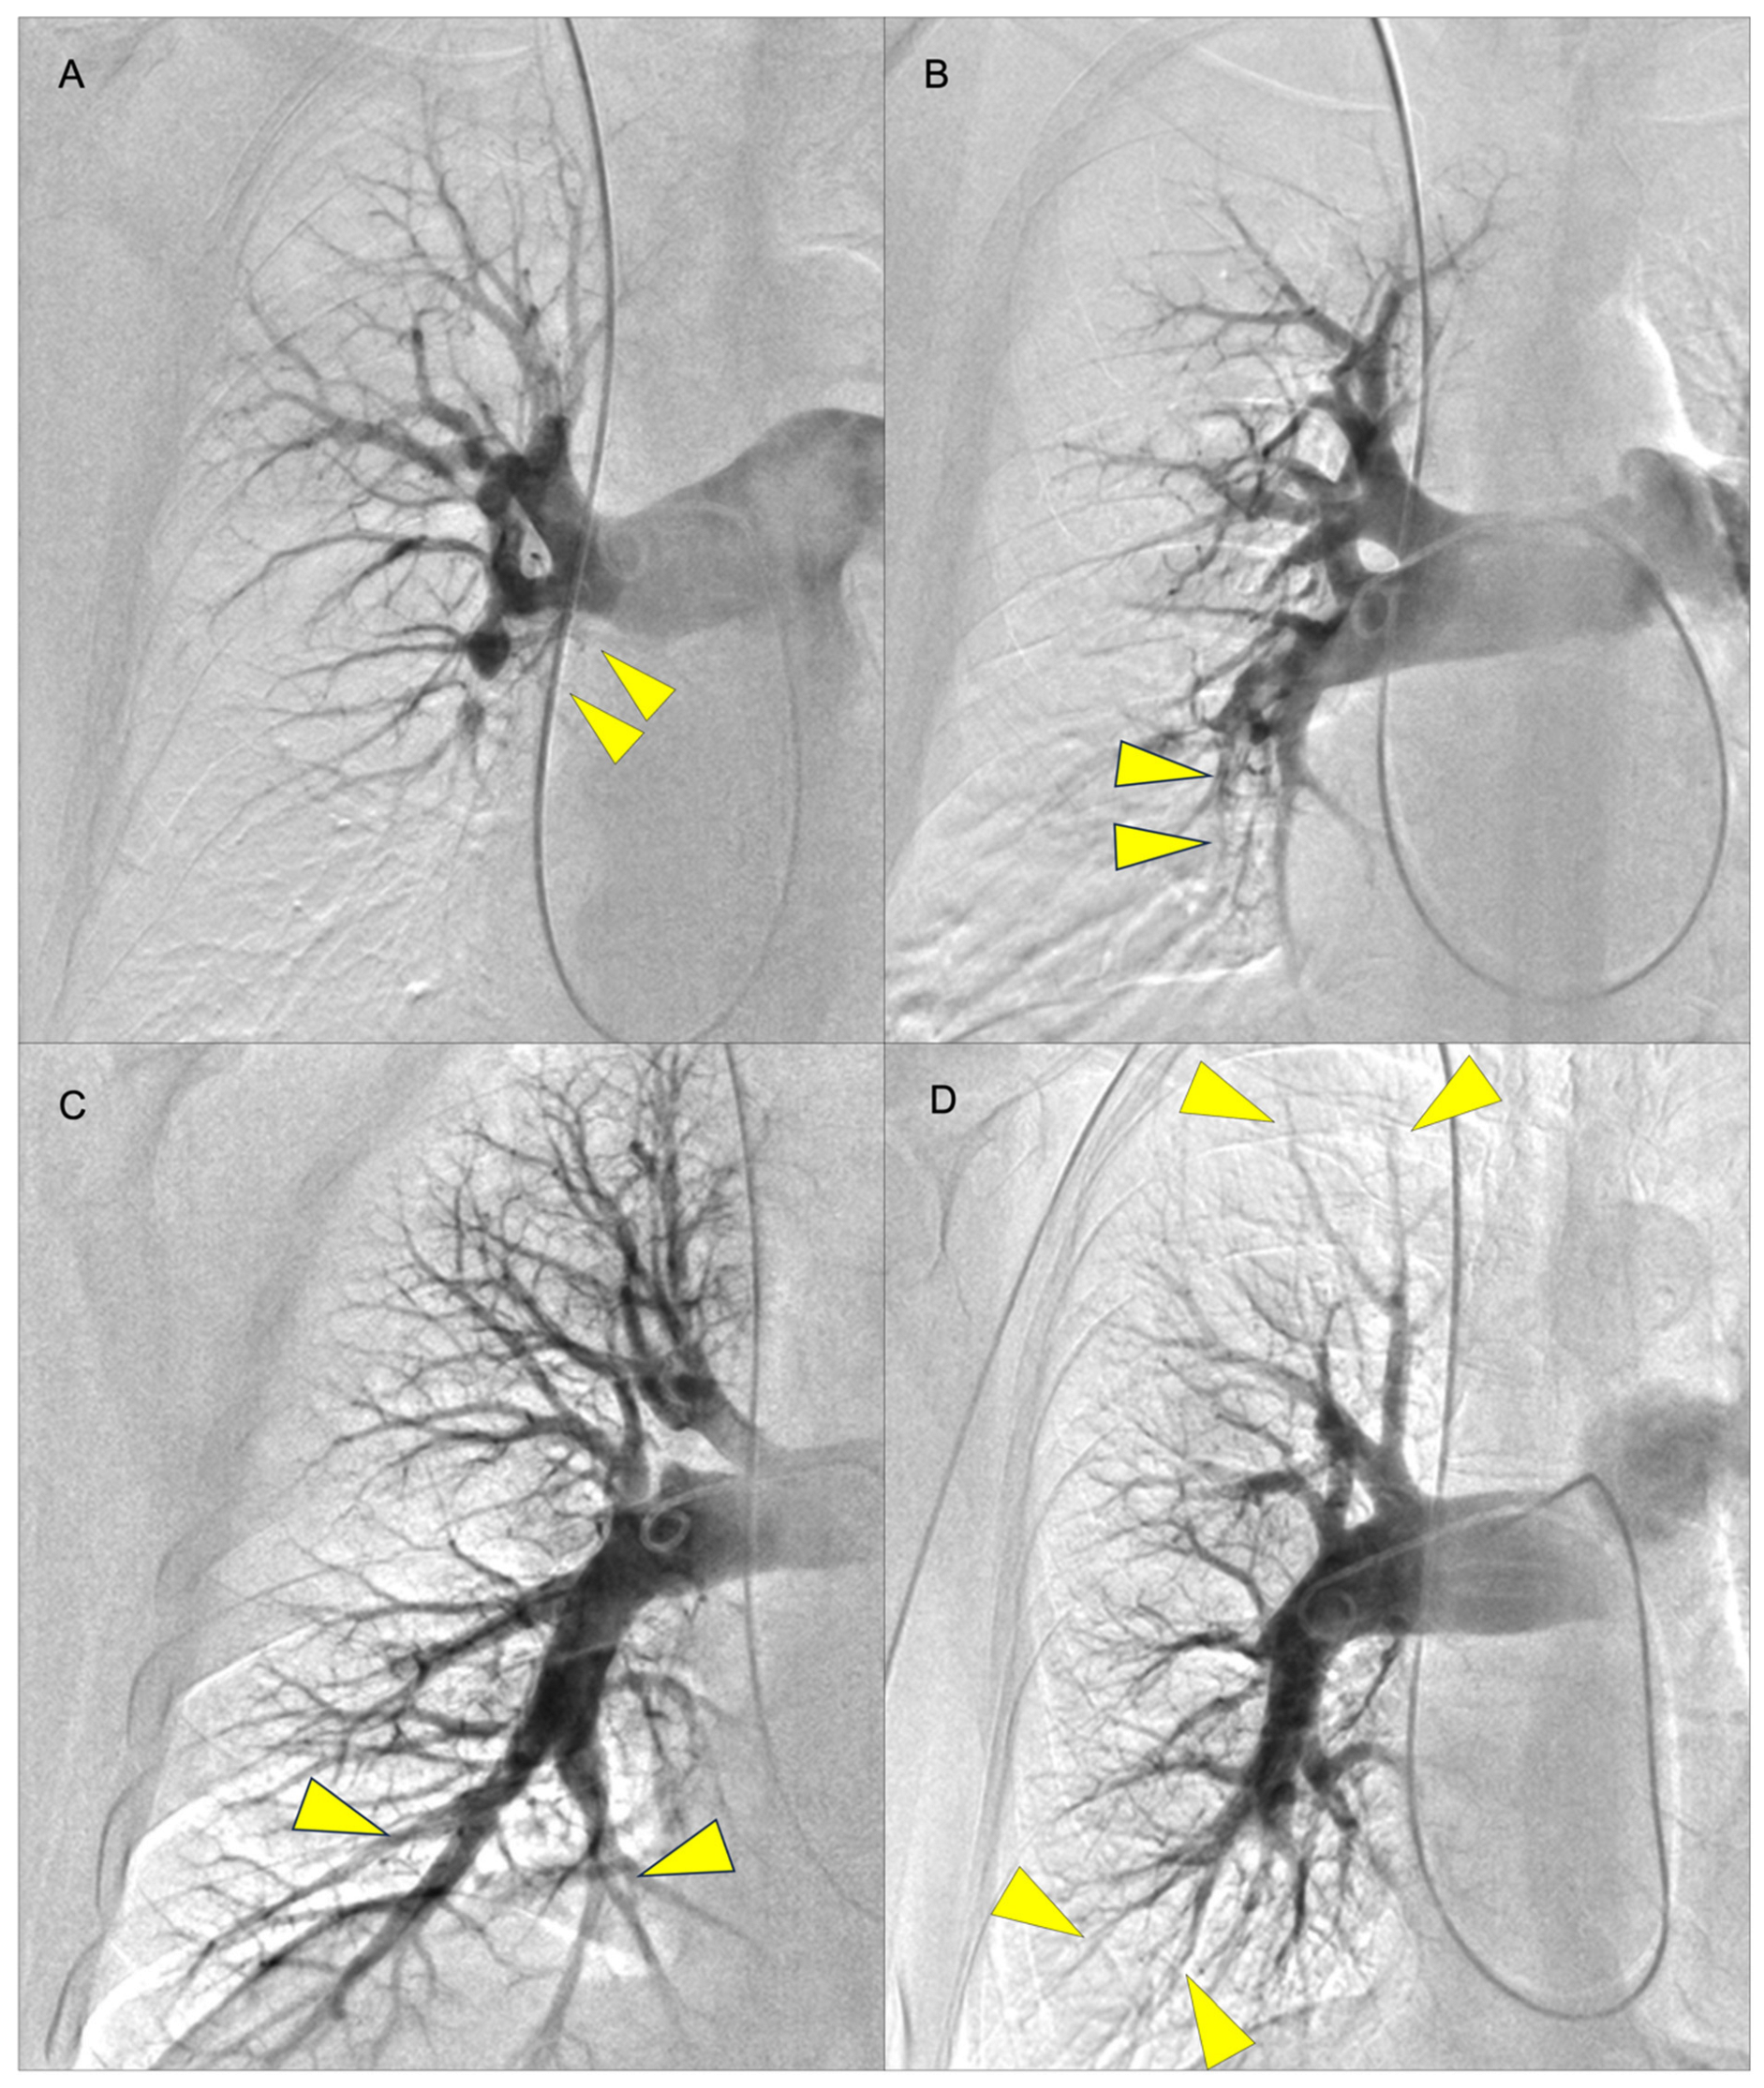

- Kawakami, T.; Ogawa, A.; Miyaji, K.; Mizoguchi, H.; Shimokawahara, H.; Naito, T.; Oka, T.; Yunoki, K.; Munemasa, M.; Matsubara, H. Novel Angiographic Classification of Each Vascular Lesion in Chronic Thromboembolic Pulmonary Hypertension Based on Selective Angiogram and Results of Balloon Pulmonary Angioplasty. Circ. Cardiovasc. Interv. 2016, 9, e003318. [Google Scholar] [CrossRef]